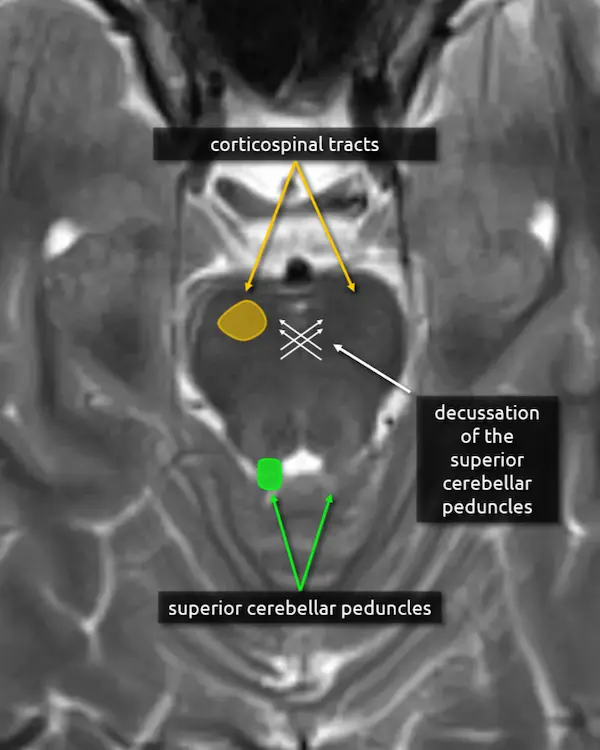

3. Decussation of the superior cerebellar peduncles

The superior cerebellar peduncles are seen in the next section, but they cross at this level in the center of the midbrain as the fibers travel superiorly.

The fibers of the superior cerebellar peduncles are highly organized causing water molecules to move along the myelin sheaths in relatively uniform directions (i.e. anisotropy). This often causes mild physiologic diffusion restriction that may be misinterpreted as an infarction. Nonetheless, infarction in this region can occur characterized by bilateral cerebellar ataxia called Wernekinck commissure syndrome, which is highly unlikely without supporting clinical history. Absence of this decussation occurs in Joubert syndrome and other ciliopathies, producing a "molar tooth" appearance of the midbrain.

1. Decussation of the superior cerebellar peduncles

2. Superior cerebellar peduncles

The superior cerebellar peduncles are the most superior of the three paired white matter bundles that connect the cerebellum to the brainstem. Their fibers are mostly efferent, beginning at the dentate and emboliform nuclei of the cerebellum and terminating at the contralateral thalamus and the red nucleus, located in the upper midbrain (see level 3).

Atrophy of the superior cerebellar peduncles can be seen in several conditions, such as progressive supranuclear palsy and other Parkinsonian disorders.

3. Corticospinal tracts

The corticospinal, corticobulbar, and corticopontocerebellar tracts continue inferiorly from the cerebral peduncles.

Lesions of the corticospinal tracts will cause motor deficits of the body and limbs. Sparing or involvement of the corticospinal tracts is a characteristic finding of several conditions, e.g., sparing of the corticospinal tracts is responsible for the "trident sign" of osmotic demyelination syndrome. The corticobulbar tract is located along the medial aspect and can be selectively damaged at this level, producing facial weakness.